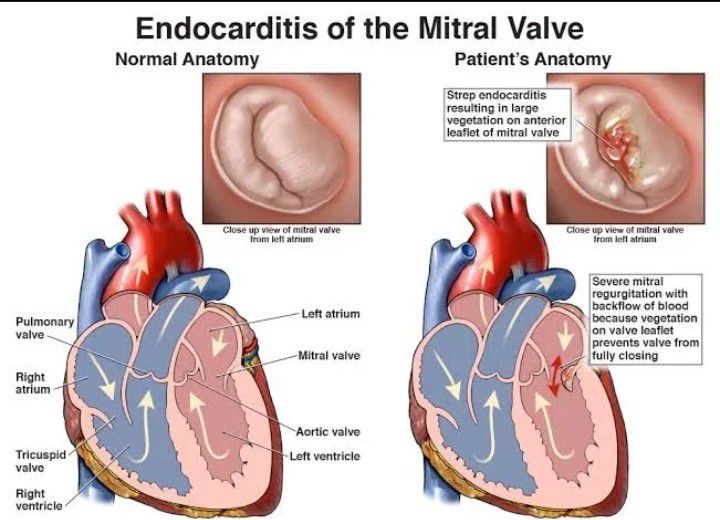

Пороки сердечно-сосудистой системы: виды и признаки